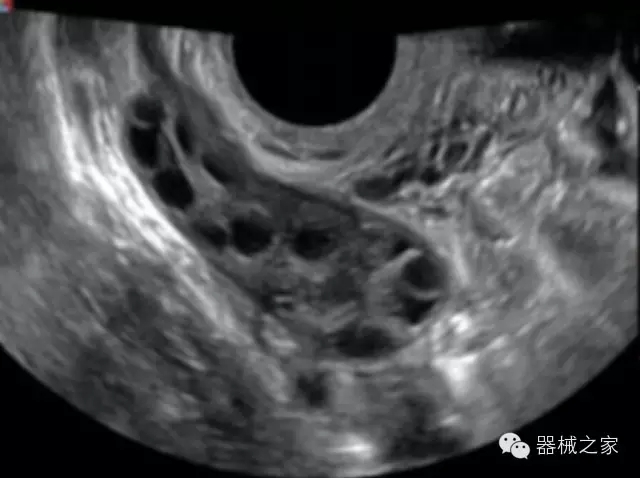

·完整的3D/4D臨床應(yīng)用,STIC, MCUT 和Auto NT等滿足產(chǎn)科所有應(yīng)用;

·更高的HQ羊膜腔鏡成像技術(shù)精細(xì)觀察每一個(gè)暗區(qū)細(xì)節(jié);

·高效3D/4D成像技術(shù):高速的4D幀頻,豐富的3D成像模式,智能斷層切片功能;